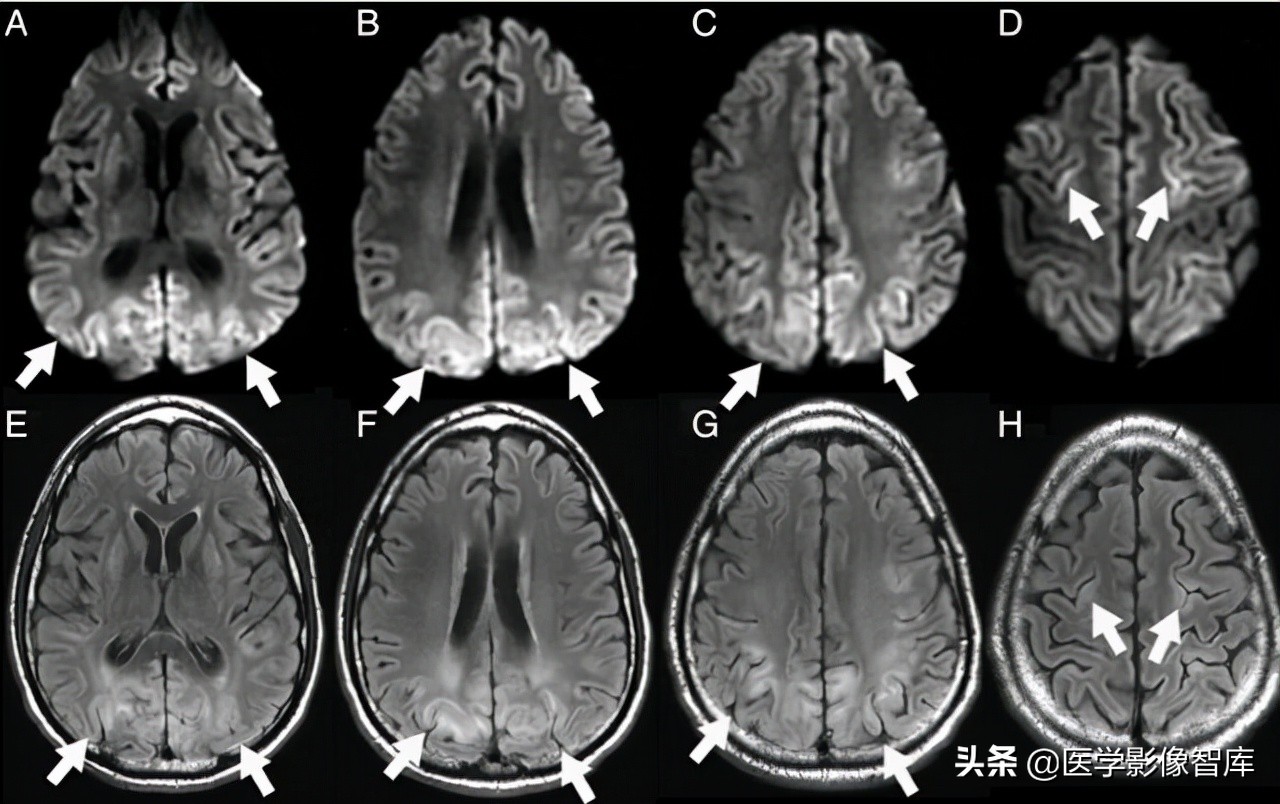

线粒体脑肌病是一组累及多系统的复杂疾病,伴有广泛的生化和遗传缺陷。线粒体脑肌病伴高乳酸血症和卒中样发作(MELAS)是研究相对较多的一类线粒体脑肌病。卒中样发作是 MELAS 的主要临床特征。尽管 MELAS 卒中样发作常在病程早期快速而完全的恢复,可是一旦第一次卒中样发作发生,患者的神经功能状态会持续恶化。卒中样发作在临床上可表现为多种神经系统症状,如癫痫发作、头痛、意识状态改变、局灶性无力、视力下降、感觉缺失、构音障碍和共济失调。典型的 MELAS 磁共振病变多分布在皮质和皮质下白质,深部白质不受累,表现为 T2WI、DWI 高信号类似卒中样表现。磁共振波谱可检测到梗死灶及其他脑部未受累区域中乳酸的存在。典型磁共振表现如图 4 所示。

图 4 MELAS 患者,A 为 DWI,可见皮层 / 皮层下 DWI 高信号,B 为 ADC 图,可见病灶低信号,C 为 FLAIR,可见病灶高信号,D 为该患者的慢性期 FLAIR,可见病灶几乎消失,受累部分脑组织萎缩